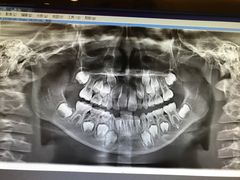

• 天使口腔门诊部(上海店)

• -天使口腔门诊部(上海店)